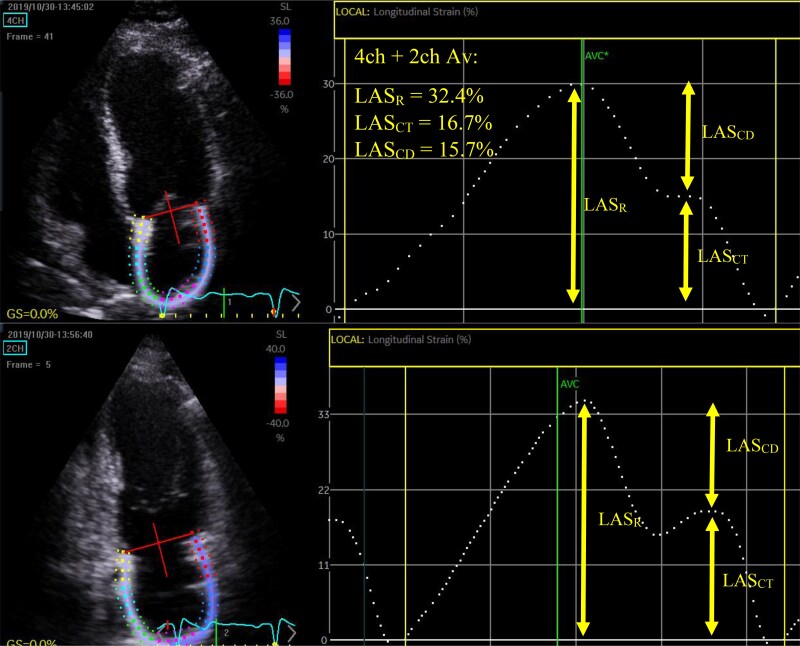

Methods and results: Fifty-six AFD patients were age- and sex-matched to 56 healthy controls. LV global longitudinal strain (GLS) and LA reservoir strain (LASR) were significantly lower in male (GLS: 19.38[3.21] vs. 17.8[7.0], P = 0.009; LASR: 38.07 ± 6.67 vs. 31.12 ± 6.76, P = 0.003) and female (GLS: 20.58 ± 1.63 vs. 19.29 ± 1.67, P = 0.003; LASR: 38.77 ± 7.43 vs. 33.13 ± 6.06, P < 0.001) AFD patients compared with controls. Reduced strain parameters were also seen in female AFD patients with normal wall thickness (GLS: 20.88 ± 1.74 vs. 19.72 ± 1.53, P = 0.037; LASR: 40.09 ± 7.15 vs. 34.79 ± 6.20, P = 0.004). 53/56 AFD patients had a median follow-up of 43[81] months; 11/53 experienced an adverse cardiovascular event (i.e. cardiac death, myocardial infarction, arrhythmias, stroke. and heart failure). LV wall thickness, LAVImax, and LV GLS displayed good sensitivity and specificity for adverse cardiac events. A prognostic risk decision tree comprising of these parameters demonstrated good predictive value for adverse events (AUC = 0.910).

Conclusion: We demonstrate differences in LV and LA echocardiographic parameters in AFD patients compared with healthy controls, including female AFD patients with normal LV wall thickness. A prognostic risk decision tree stratified AFD patients into three groups with the highest risk group demonstrating more AFD-related adverse events.